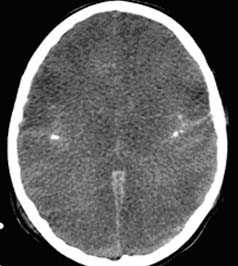

КТ позволяет последовательно изучить мягкие ткани головы, кости черепа, вещество мозга, эпидуральные, субдуральные, субарахноидальные пространства, цистерны основания и желудочки мозга:

- определить степень сдавления или дислокации головного мозга объемным процессом,

- выявить наличие диффузного или перифокального отека и его степени,

Визуализация минимальных количеств излившейся свежей крови, уверенная дифференциация ее от других внеклеточных жидкостей, слежение за динамикой отека и набухания головного мозга, некроза и восстановления его структур с одновременным распознаванием переломов костей черепа, особенно его основания, составляют преимущества КТ перед магнитно-резонансной томографией.